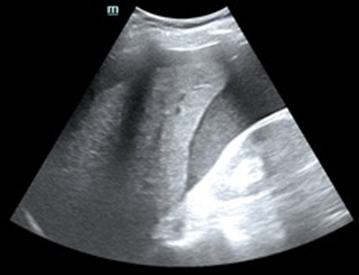

Tras varias horas en observación el paciente comienza con tendencia a la hipotensión. Permanece en observación y monitorización persistiendo hipotensión arterial con buena ventilación bilateral en la auscultación pulmonar. En la exploración abdominal presenta dolor y defensa a la palpación profunda en hipocondrio izquierdo. Se realiza Ecografía clínica a pie de cama del paciente descartando hemoneumotótax y derrame pericárdico; al explorar el abdomen se objetiva líquido libre en espacio de Morrison y eje espleno renal, con imagen compatible con rotura del parénquima esplénico. Gasométricamente se objetiva anemización con caída de cifras de Hb de 15,7 g/dl en análisis inicial a 13,8 g/dl. Se solicitan pruebas cruzadas, se reservan hemoderivados y se contacta con cirugía para traslado del paciente a quirófano.